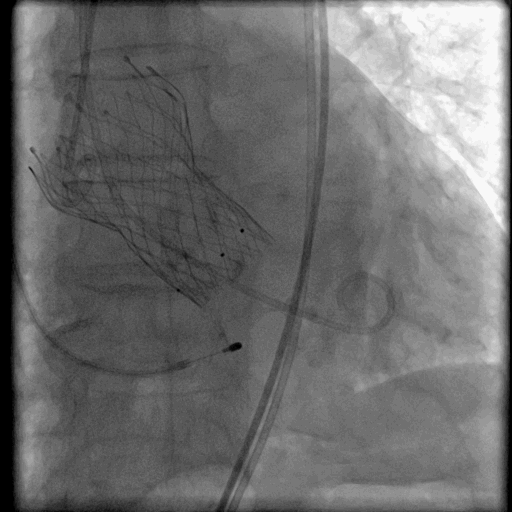

TAVR瓣膜释放过程

通过22F血管鞘置入VenusA-Plus瓣膜,并顺利过主动脉弓,跨越瓣膜,造影确定瓣膜位置, 确定瓣膜Mark点与瓣环平行,逐步释放部分瓣膜,瓣膜裙边展开,保持瓣膜位置,造影提示瓣膜位置良好,开始慢速释放瓣膜,待裙边完全展开,开始130次/分快心室率起搏,确保瓣膜释放过程位置稳定,继续释放瓣膜,再次造影提示位置良好,快速释放瓣膜。

回收置入器,瓣膜释放后因存在瓣周漏,故采用23mm球囊进行后扩张一次,术后TEE提示,支架瓣膜展开基本完全,TEE及造影提示轻度PVL。

瓣膜血流动力学效果满意。测量左心室压力136/2mmHg,升主动脉压力134/55mmHg,跨瓣压力<5mmHg,手术效果满意。

TAVR-VenusA-Plus植入后